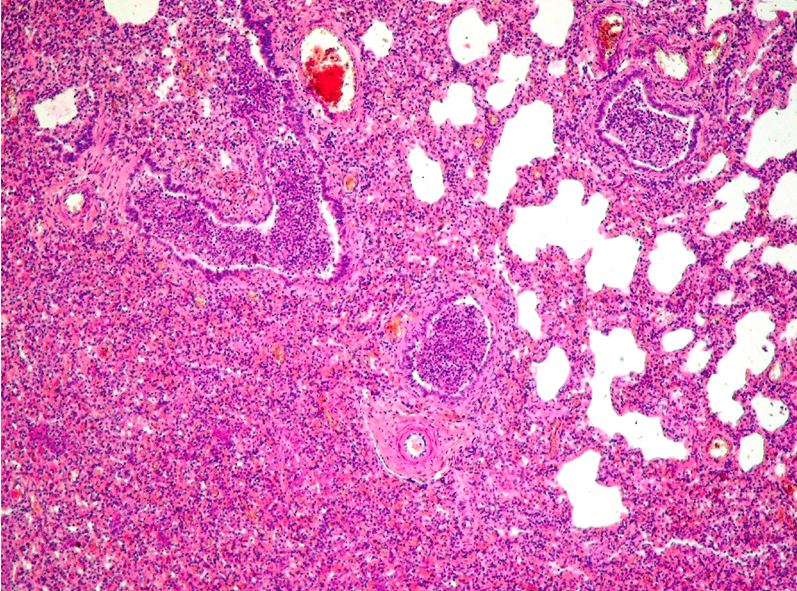

Identify lesion

Bronchopneumonia

identify lesion:

What changes can be observed in this lesion and what are the 4 Stages?

-Multifocal changes-

Four stages, but we can observe different stages in every focus.

Pneumonia has 4 stages:

Congestion

Red hepatization

Gray hepatization

Resolution